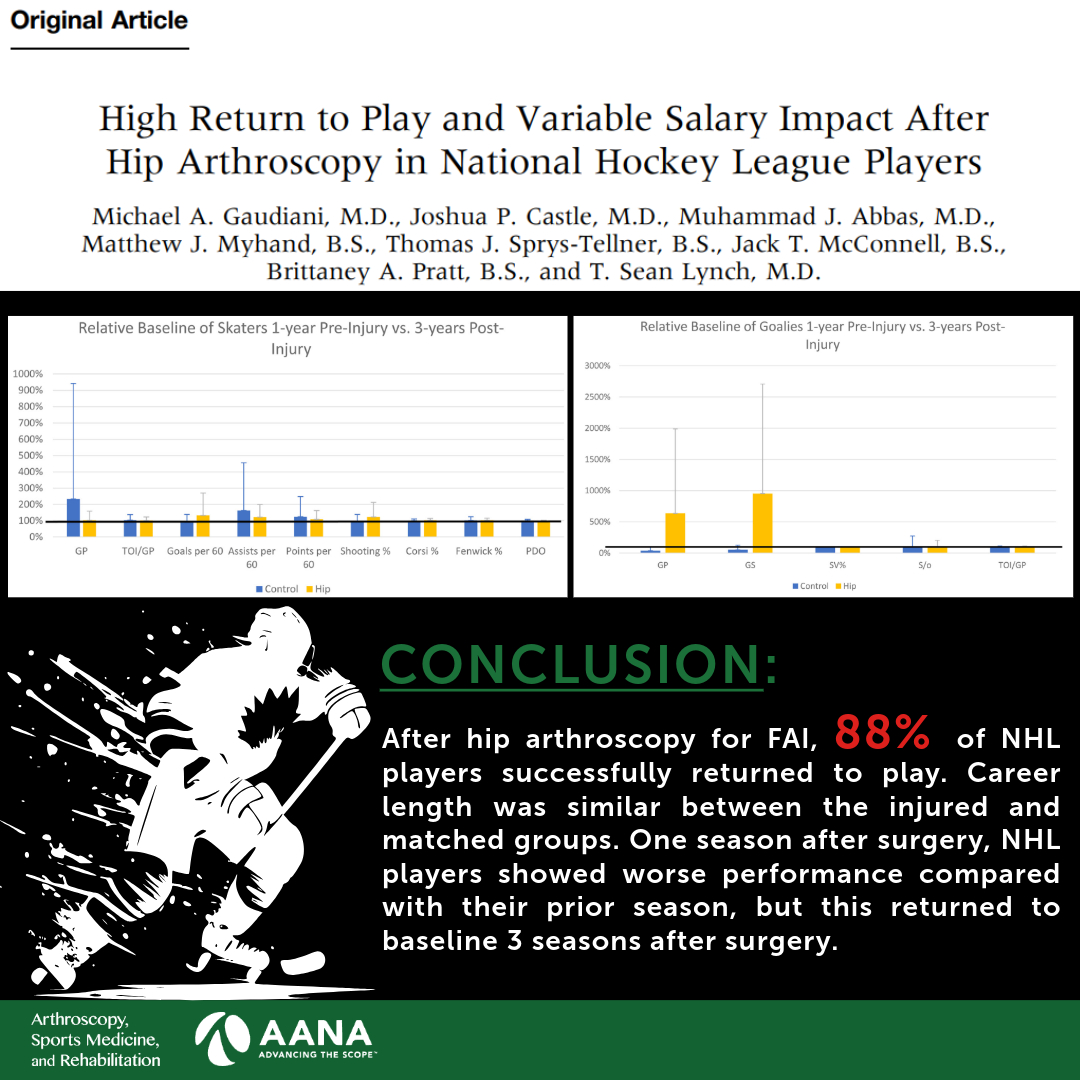

🆕‼️ Sprint Running Mechanics & Hamstring Injury Risk ‼️🆕 Our latest research in British Journal of Sports Medicine (BJSM) explores whether sprint mechanics are linked to past and future hamstring injuries in professional footballers. What did we find? And why does this matter? 🧵👇 bjsm.bmj.com/content/early/…